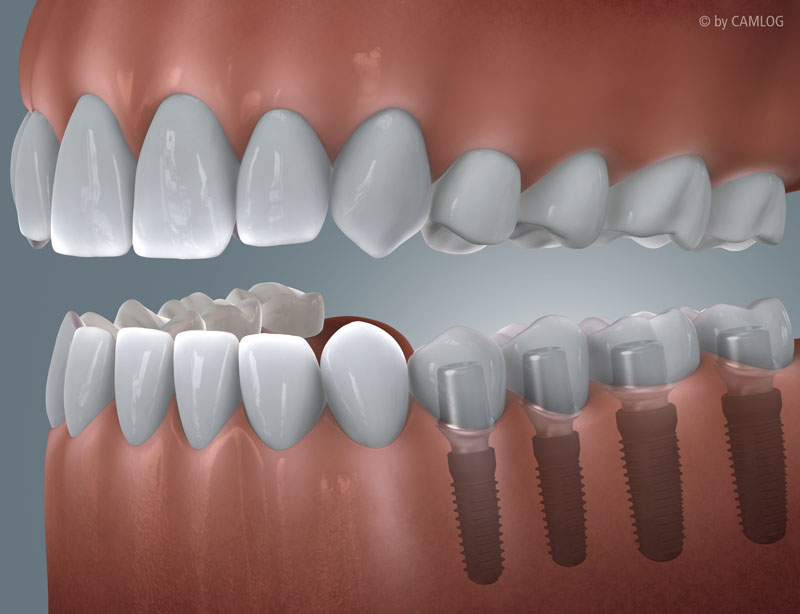

Mit den Methoden der modernen Implantatprothetik lassen sich ästhetisch und funktionell hochwertigste Versorgungen erzielen:

Mit den großen Fortschritten im Bereich der zahnärztlichen Implantologie wird der Traum nach festen Zähnen in vielen Fällen möglich mit dem Konzept "All on four/six".